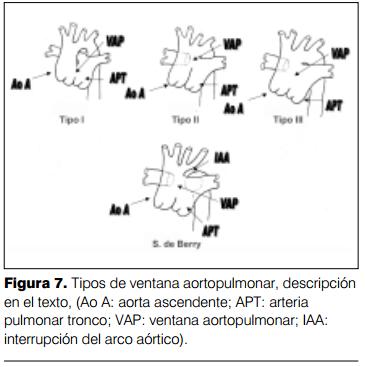

La ventana aortopulmonar es una anomalía poco frecuente y ocurre en el 0,1-0,2% de todas las cardiopatías congénitas (1,2). Consiste en una amplia comunicación entre la aorta ascendente y el tronco de la arteria pulmonar debido a una separación incompleta de los sectores derecho e izquierdo del conotronco, por encima del plano de las válvulas sigmoideas aórtica y pulmonar (3,4). La ventana aortopulmonar puede estar ubicada entre las válvulas sigmoideas y la bifurcación del tronco pulmonar (tipo I), o sobre la bifurcación del tronco pulmonar usualmente con origen de la arteria pulmonar rama derecha directamente de la aorta ascendente (tipo II), o asociar los tipos I y II (tipo III), o asociar al tipo III interrupción del arco aórtico: síndrome de Berry (5,6) (figura 7).